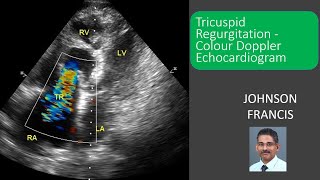

Colour Doppler in Tricuspid Regurgitation Tricuspid Regurgitation - Colour Doppler Echocardiogram

Tricuspid Regurgitation - Colour Doppler Echocardiogram Colour Doppler in Tricuspid Regurgitation

Colour Doppler in Tricuspid Regurgitation Tricuspid Regurgitation - Colour Doppler Echocardiogram

Tricuspid Regurgitation - Colour Doppler Echocardiogram Colour Doppler in Tricuspid Regurgitation